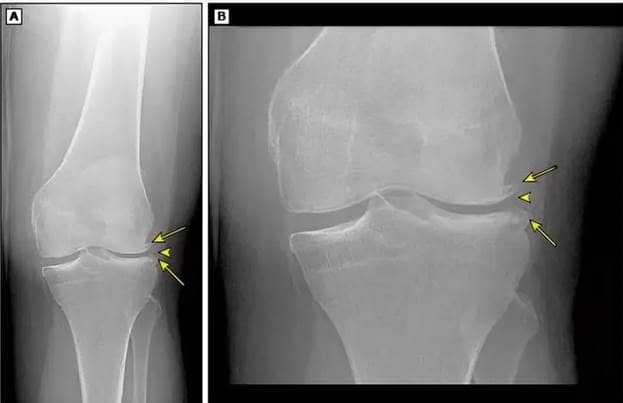

Krew usuwa sole ze stawów. Jeśli słabo krąży, sole się nagromadzą. Są to sole wapniowe i sodowe, które znajdują się w prawie wszystkich produktach i które są niezbędne dla człowieka. Jednak gdy odkładają się w stawach, prowadzą do powstania twardych narośli kostnych (osteofitów) na powierzchni stawu. Z czasem mogą się powiększać i ściskać zakończenia nerwowe. Prowadzi to do silnego bólu. Zwykle ludzie nie mogą znieść tego bólu i zwracają się do profesjonalistów. Ale jeśli ból jest bardzo silny, tylko operacja może pomóc. Jeśli ból jest rzadki i nie jest silny, można go rozwiązać za pomocą metod terapeutycznych, ale należy się spieszyć.

Narośle kostne w stawie kolanowym

Narośle kostne w stawie kolanowym